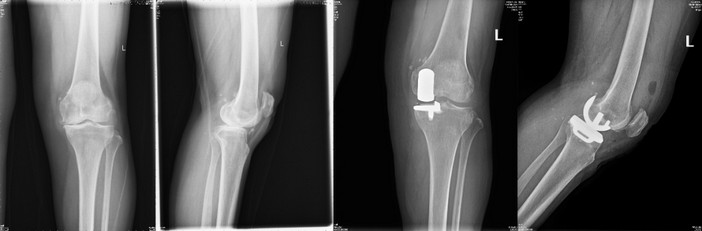

手術(shù)治療

蔡××,女,61歲,單側(cè)膝關(guān)節(jié)骨關(guān)節(jié)炎行膝關(guān)節(jié)單髁置換術(shù),術(shù)后第2天即下地行走。